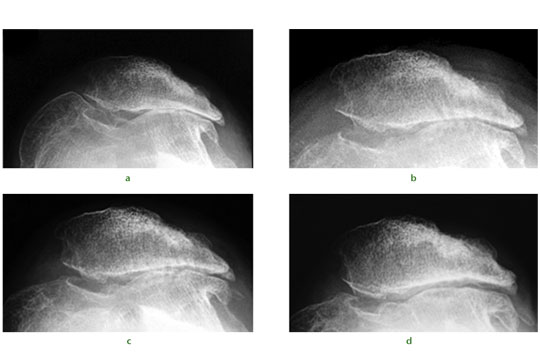

Fig. 1 A 34-year-old female presented with recurrent dislocation of her patella as an adolescent. Radiographs were taken a) pre-operatively, and b) immediately post-operatively showing evidence of subchondral drilling. Radiographs at c) six months and d) two years showed a progressive reappearance of the lateral patellofemoral articulation.

We have published some early results of stem cell therapy for osteochondral defects. A typical case would be that of a 34-year-old ex-orthopaedic nurse presenting following multiple previous operations for patellar dislocation and complete loss of the lateral patellofemoral articular facet cartilage (Fig.1a). Rather than a total knee replacement she underwent arthroscopic debridement, lateral patellar release, and subchondral drilling. Intra-operative findings were of multiple grade III and IV lesions over the entire patellofemoral joint. The traditional surgical approach of osteophyte removal and subchondral drilling over the entire patellofemoral joint (Fig.1b) was performed and supplemented with intra-articular injections of PBSC with HA. Over the following two years, radiographs illustrate progressive reappearance of the lateral patellofemoral joint space (Figs 1c and 1d). At two years after surgery, the patellofemoral crepitation was minimal and the knee function gradually improved.5